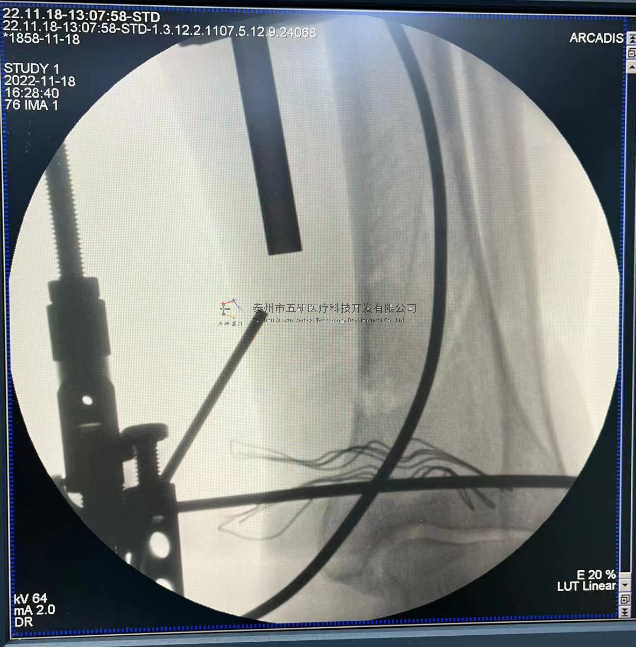

【影像圖片—術(shù)后】

【手術(shù)資料】